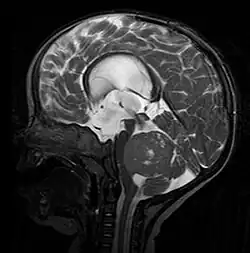

Medulloblastom in der MRT, sagittal T2w. Der Tumor dehnt sich im Wesentlichen innerhalb des 4. Ventrikels aus (dunkel, untere Bildmitte).

In der Computertomographie (CT) und Magnetresonanztomographie (MRT) stellen sich Medulloblastome als solide Raumforderungen mit ungleichmäßiger Kontrastmittelaufnahme dar. Sie wachsen meist vom Boden des 4. Ventrikels in den Kleinhirnwurm. Im nativen CT (also ohne Kontrastmittel) ist der Tumor gering hypodens (dunkel), nach Kontrastmittelgabe hyperdens (hell). Im MRT kann man den Tumor aufgrund seiner inhomogenen, symmetrisch in der Mittellinie gelegenen Lage in kraniokaudaler Ausdehnung mit hypointensem (dunklen) Signal in T1 und hyperintensem (hellem) Signal in T2 (weil vermehrt wasserreich) gut erkennen. Oft kommt es zu einer Obstruktion der Ventrikel; als Folge dessen kommt es zum Hydrocephalus. Bei sehr jungen Patienten kann sich dies durch verbreiterte Kalottennähte (Wolkenschädel) zeigen, welche als Konsequenz des steigenden Hirndrucks auseinanderweichen.